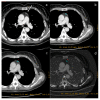

Dual-energy computed tomography (DECT) is one of the most promising technological innovations made in the field of imaging in recent years. Thanks to its ability to provide quantitative and reproducible data, and to improve radiologists' confidence, especially in the less experienced, its applications are increasing in number and variety. In thoracic diseases, DECT is able to provide well-known benefits, although many recent articles have sought to investigate new perspectives. This narrative review aims to provide the reader with an overview of the applications and advantages of DECT in thoracic diseases, focusing on the most recent innovations. The research process was conducted on the databases of Pubmed and Cochrane. The article is organized according to the anatomical district: the review will focus on pleural, lung parenchymal, breast, mediastinal, lymph nodes, vascular and skeletal applications of DECT. In conclusion, considering the new potential applications and the evidence reported in the latest papers, DECT is progressively entering the daily practice of radiologists, and by reading this simple narrative review, every radiologist will know the state of the art of DECT in thoracic diseases.